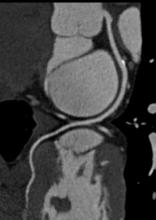

Since entering the market in 2001, PET/CT (positron emission tomography/computed tomography) has come a long way in combining the benefits of individual PET and CT imaging. Last year saw the release of several new innovative technologies, marking improvements on previous generations of PET/CT, such as continuous data acquisition and bed motion, as well as higher image resolutions.

A new technique that brings computed tomography (CT) imaging into the operating room will allow surgeons to precisely demarcate and remove small sub-centimeter lung nodules, leaving as much healthy tissue as possible, according to Raphael Bueno, M.D., of Brigham and Women's Hospital in Boston.